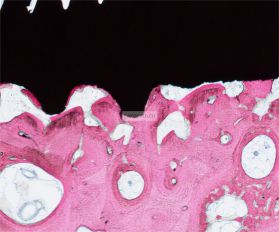

将包埋好的硬组织树脂块,用EXAKT 硬组织切片机先切一个200um的厚片,然后再通过EXAKT 硬组织磨片机将其磨到20-30um薄片,样本是已经硬组织包埋好的含金属的动物样本。

具体步骤:包埋块修开切面抛光-平行粘片装置粘片-硬组织切片机切片-硬组织磨片机磨片抛光成片。

4、染色处理

针对不同的病理阅片指标需求,行HE染色、Masson染色、亚甲基蓝-酸性品红染色、VG染色、Movat染色等。